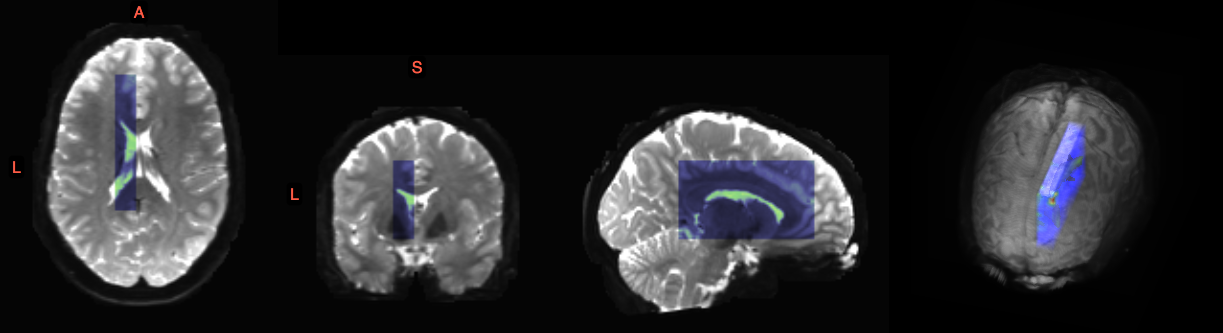

Refer to caption

Figure 13: Selected region of interest for synthetic warp experiments (blue) overlaid on the b0subscript𝑏0b_{0} image of HCP subject 103818.

The DWI data used in this experiment is shown in Figure 13, where the region of interest (ROI) is the blue overlay on the subject’s b0subscript𝑏0b_{0} image. An ROI of the brain is used to improve the visualization of the results. The ROI was chosen at the edge of the corpus callosum (CC) in the left hemisphere due to the characteristic C-shape of the CC and the intersection with other well-known structures e.g. the cingulum. Furthermore, the ROI is in an area with crossing fiber tracts and is near the cortex. A b=1000𝑏1000b=1000 DWI volume is used with a ROI size 11×71×4111714111\times 71\times 41 at 1.25mm isotropic voxels with 90 directions. Only the central sagittal slice along with corresponding ODFs is visualized (Figure 14a), while the deformation is applied to the whole ROI. The deformation field for the central slice is shown in Figure 14b.